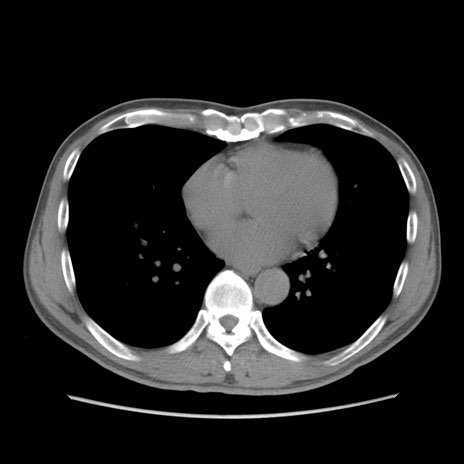

症例56 CT(横断像)